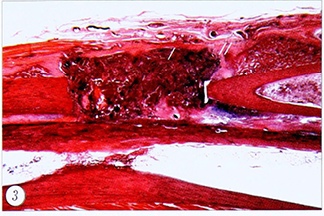

Через 2 нед после имплантации ФФКТ с размером частиц 0,2—0,7 мм в дефект лучевой кости рентгенологически сохраняется слабоконтрастная тень. Гистологическое исследование: костный дефект заполнен соединительной тканью, которая окружает фрагменты фетальной костной ткани, распределенные относительно равномерно между костными отломками (рис.З). Фрагменты

имеют неправильную, округлую или продолговатую форму. Структура их костного вещества гомогенна. Промежутки между костными пластинками фрагментов заполнены клеточными элементами. Костномозговые каналы костных отломков частично или полностью закрыты волокнистой соединительной тканью, которая не только заполняет дефект, но и выходит за анатомические границы удаленного костного сегмента диафиза. С наружной стороны этот волокнисто-клеточный комплекс ограничен плотной оформленной соединительной тканью. Контуры отломков неровные (с «зазубринами») и подчеркнуты базофильной линией. В отдельных местах в непосредственной близи к краям отломков остеоциты не выявляются. На периостальной и эндостальной поверхности обнаруживаются костные регенераты губчатого строения. Наибольшую толщину они имеют у краев опилов. По мере удаления от дефекта слой новообразованной кости постепенно становится все тоньше, переходя в «спокойную» надкостницу. В то же время встречаются участки интактной периостальной и эндостальной поверхности в непосредственной близи к краям костных отломков. В кортикальных пластинках костных отломков встречаются расширенные центральные каналы и сосуды с агрегированными эритроцитами. Волокнисто-клеточный комплекс с фрагментами фетальной кости, заполняющий костный дефект, может непосредственно контактировать с поверхностью локтевой кости.

Рис. 3. Предплечье кролика, 2 нед после операции, 1-я опытная группа. Дефект лучевой кости заполнен ФФКТ (/) и соединительной тканью (//).

Здесь и на рис. 4~7: гистологический препарат, окраска гематоксилином и эозином, ув. 10.